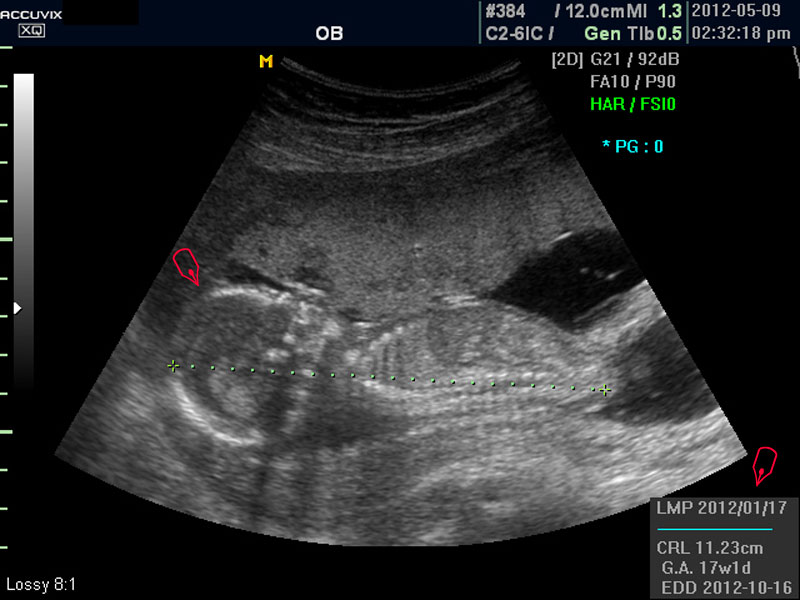

보통 태아의 발육은 머리부터 엉덩이까지의 크기인 CRL(Crown Rump Length의 약자)이 정상인가 하는 것과 태아의 두상 크기인 BPD(BiParietal Diameter의 약자)가 정상 범위에 들어 있는가 하는 것으로 판단합니다.

화면에서 좌측이 태아 머리 부분으로 빨간 펜으로 표시되어 있습니다.

초음파 상 태아의 머리가 좌측인가 우측인가 하는 것은 초음파 탐촉자의 위치를 어디에 두었느냐에 따라 다른 것 뿐으로 화면상 어디 위치하는 지는 중요하지 않습니다.

대신 첫번째 사진에서 보는 것처럼 태아의 전체 모습 특히 태아의 등쪽이나 복벽의 이상은 없는지 신경관 결손 등으로 인한 종괴가 있지는 않은지 관찰하며 태아의 복벽이나 등쪽은 일직선으로 매끈하게 보이는 것이 정상입니다.

첫번째 사진에서는 하지 부분은 대퇴부만 일부 보이며 이는 태아가 다리를 구부리고 있고 팔도 이리저리 움직여 머리 위나 목 쪽으로 두는 경우가 많아서 한번에 전체 모습을 찍기가 어려운 경우가 많습니다.

모든 사진에서 우측 하단에는 기본적인 발육 정보가 기록되는데 세번째 사진에서 빨간 펜으로 표시한 부분이며 그 내용의 의미는 아래와 같습니다.

2. CRL

위에 말한 태아 크기를 말하는 지표로 실제 수치가 표시됩니다.

3. GA

Gestational Age의 약자로 우리말로는 임신 주기라고 하며 CRL이나 BPD등을 기준으로 했을때 임신 몇주 며칠에 해당하는 지 나타낸 것입니다.

5.EDD

Estimated Due Date의 약자로 초음파 측정치를 바탕으로 산출한 출산 예정일입니다.